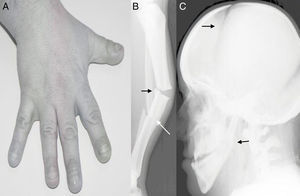

Exposición del caso clínicoSe trata de un paciente de 34 años de edad que fue visto en urgencias del Complejo Asistencial Universitario de León tras una caída casual. El paciente presentaba una estatura baja, fascies sindrómica, uñas distróficas, manos y dedos pequeños (fig. 1A). El estudio radiográfico inicial de la pierna del paciente presentaba una fractura de tercio medio de tibia y peroné transversa pura, sobre un hueso con corticales muy gruesas y gran masa ósea (fig. 1B). Posteriormente se completó el estudio radiográfico con una radiografía de cráneo para confirmar el diagnóstico de picnodisostosis, donde se puede observar un ángulo mandibular obtuso, y las fontanelas craneales abiertas (fig. 1C).

El paciente presentaba una estatura baja, fascies sindrómica, uñas distróficas, manos y dedos pequeños (A). El estudio radiográfico inicial de la pierna del paciente presentaba una fractura de tercio medio de tibia y peroné transversa pura, sobre un hueso con corticales muy gruesas y gran masa ósea (B). Se completó el estudio radiográfico con una radiografía de cráneo para confirmar el diagnóstico de picnodisostosis, donde se puede observar un ángulo mandibular obtuso, y las fontanelas craneales abiertas (C).